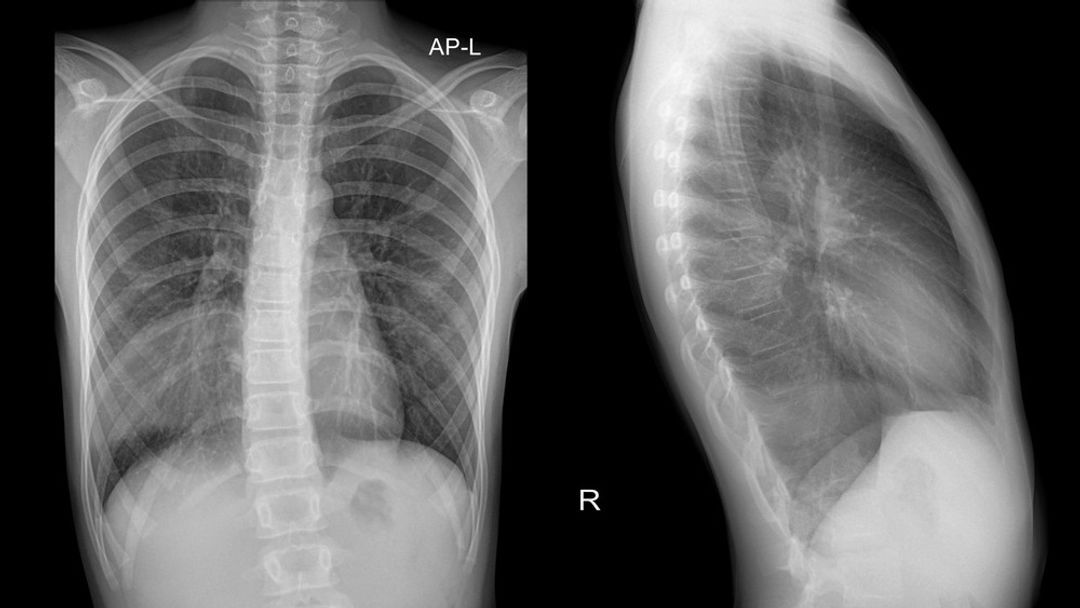

Pneumonia

X-rays can reveal areas of consolidation (whitish, dense regions) in the lungs, indicating inflammation and infection.

Chest X-rays can reveal lung masses or nodules suggestive of cancer, although further imaging (e.g., CT scans) and tissue sampling are required to confirm the diagnosis.

Chronic obstructive pulmonary disease (COPD)

X-rays can show signs of emphysema (such as hyperinflation of the lungs and flattened diaphragms) or chronic bronchitis (e.g., increased bronchovascular markings) in patients with COPD.

Pulmonary oedema

Fluid accumulation in the lungs, often resulting from congestive heart failure, can be visualised on a chest X-ray as diffuse haziness, interstitial markings (Kerley lines) and an enlarged heart silhouette.

Cardiomegaly

An enlarged heart can be identified on a chest X-ray by assessing the size and shape of the heart silhouette, potentially indicating underlying heart conditions, such as hypertrophic or dilated cardiomyopathy.